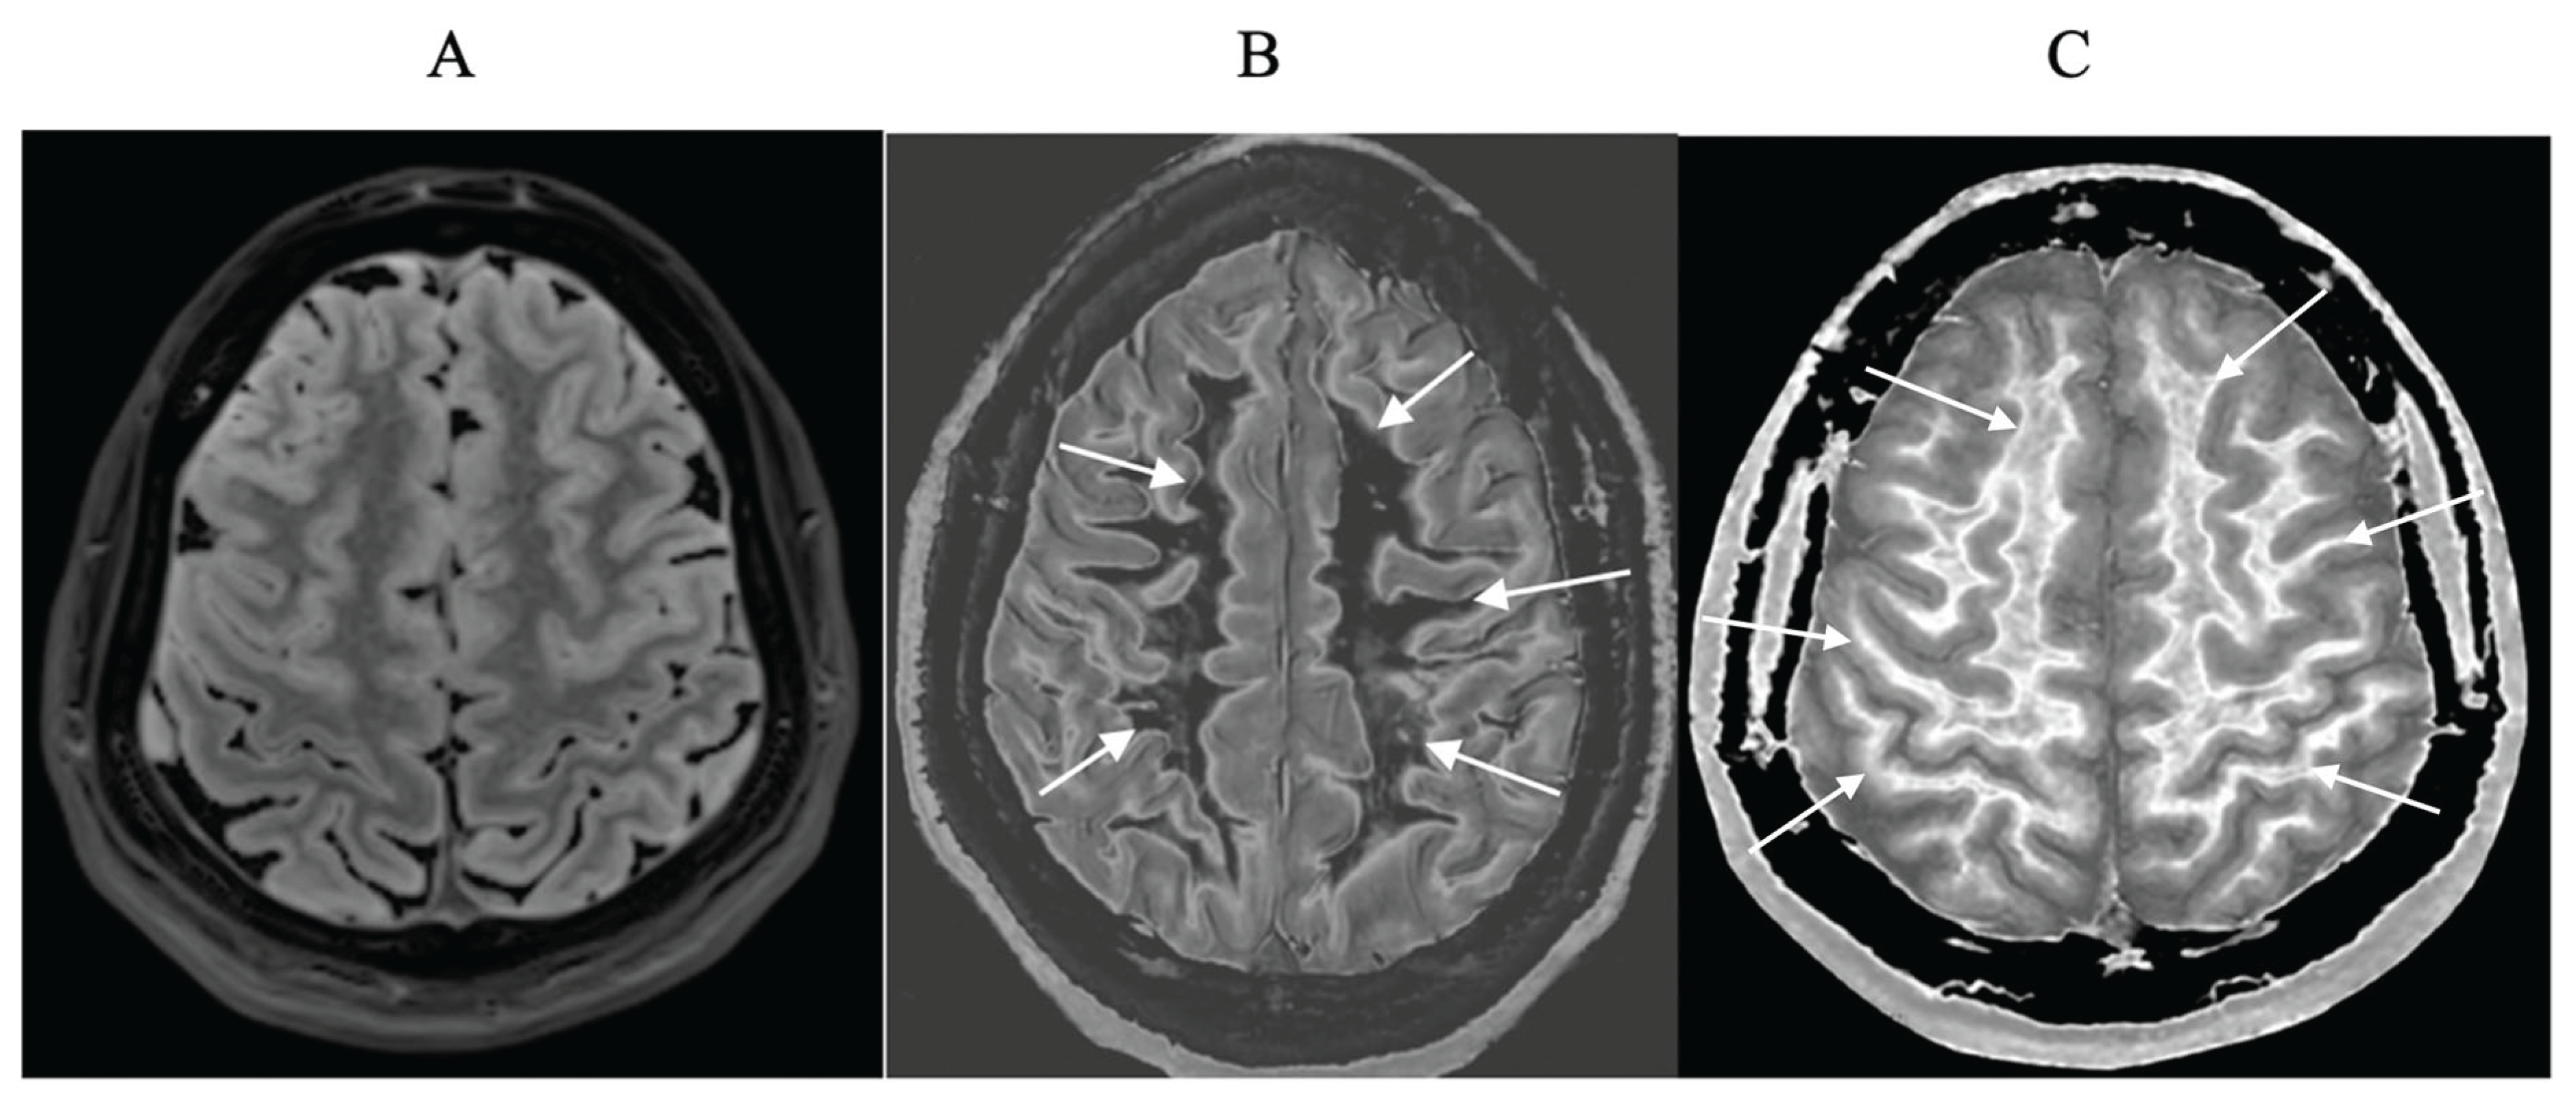

- Mild Traumatic Brain Injury (mTBI)